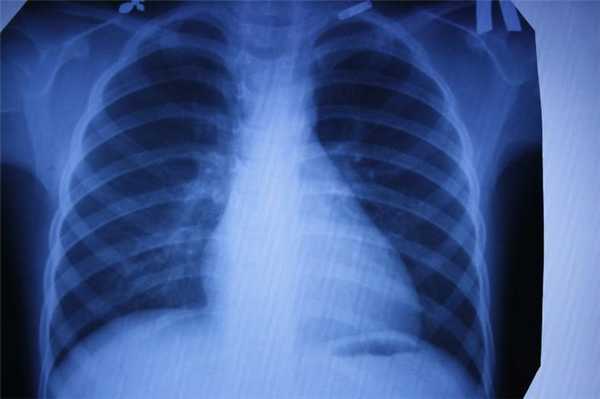

Флюорография

Ещё один тип обследования, которому регулярно все жители нашей страны. Флюорографию “изобрели” почти сто лет назад. Это своего рода ускоренная рентгенография. Учёные предложили фотографировать экран с изображением, полученным при рентгенографии. Это позволило сделать процедуру более быстрой и массовой. Скрининг-тесты начали делать всем, чтобы выявлять скрыто протекающий туберкулёз лёгких.

Главный плюс процедуры — быстрота, главный минус — качество изображения. Пациент также получает дозу облучения, а врач довольно размытую картинку, поэтому флюорографию рекомендуется дополнять анкетированием и лабораторными тестами на наличие туберкулёза.

Каждый метод дает разную информацию об исследуемых органах. Если говорить в целом, то КТ идеально «видит» легкие, и превосходит все другие методы в выявлении патологии дыхательной системы: и МРТ и рентген и флюорографию.

Для выявления патологии легких также назначают рентген и флюорографию…

Если речь идет о профилактическом осмотре, ежегодной диспансеризации, и у человека нет никаких жалоб - классическое рентгеновское исследование, которое дает меньшую, чем КТ лучевую нагрузку, можно считать достаточным. Но если пациент находится в группе риска по развитию рака легких (например, это курильщик с серьёзным стажем), лучше сразу сделать более информативную КТ. Андрей Дмитриевич Каприн, главный онколог России, рассказывает, что благодаря огромному количеству КТ- исследований легких, которые были сделаны за время пандемии, удавалось выявлять рак легких на самых ранних стадиях и множество других, не связанных с COVID-19 патологий. Низкодозовая КТ - лучший метод скрининга рака легких, она позволяет увидеть зарождающийся опухолевый процесс размером 2-3 мм и самые минимальные изменения, которые рентген может и пропустить.